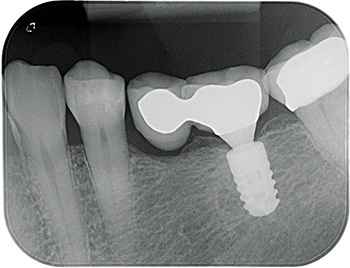

Fig. 3: Pre-op PA

So, I placed an 8 mm-long Ankylos implant into her lower left first molar site. Three months later, the prosthodontist restored it with a cantilever bridge.

Fig. 5: Restoration PA.